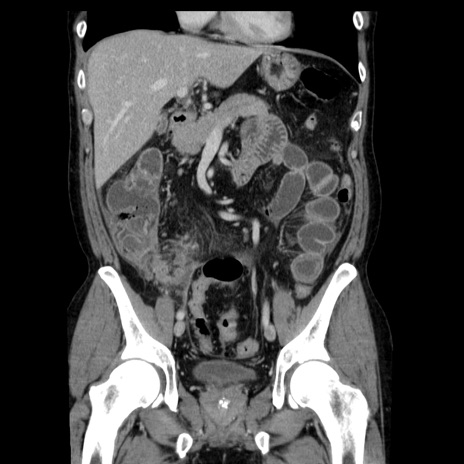

症例29(冠状断像)

【症例】40歳代男性

【現病歴】2日前から胃痛あり。徐々に周期的な激痛に変化した。本日になっても激痛があるため受診。

【身体所見】意識清明、BT 38-39℃台あり、腹部:膨満、やや硬、右下腹部に圧痛あり。

【データ】WBC 8500、CRP 23.26